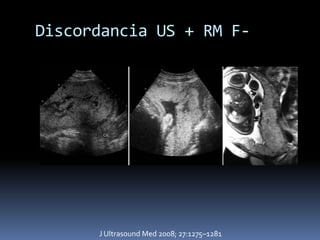

Discordancia US + RM F-

J Ultrasound Med 2008; 27:1275–1281

Discordancia US +RM F- J Ultrasound Med 2008; 27:1275–1281